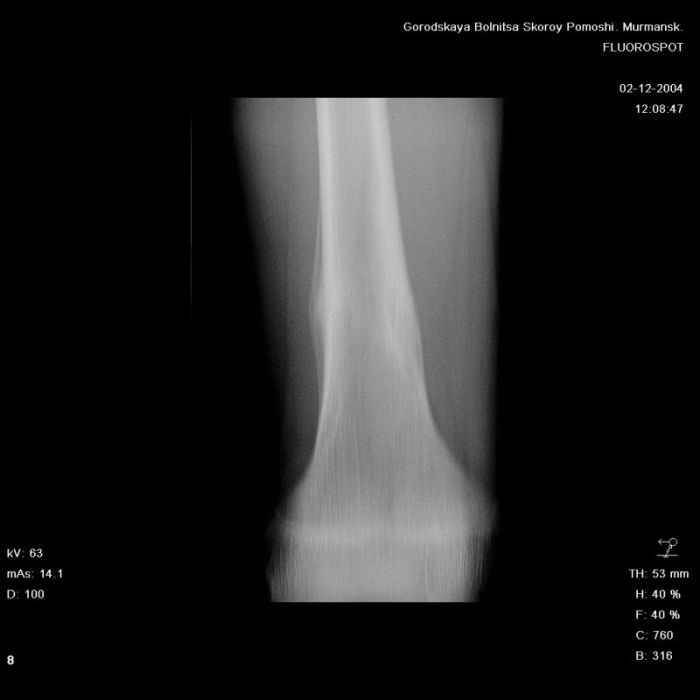

из БСМП г. Мурманск

Здравствуйте, уважаемые коллеги! Представляю вашему вниманию интересный случай и пока что непонятный для меня в диагностическом плане. На днях в наше отделение (детской ортопедии и травматологии) поступил 13-летний мальчик по направлению из поликлиники с диагнозом: остеома нижней трети правого бедра.

Анамнез практически никакой: в следствие травмы (растяжение связок коленного сустава) от 07.11.2004 выполнены Rg-граммы в травмпункте и обнаружено опухолевидное образование. Первичные Rg-граммы я не публикую, так как они заметно худшего качества, да и динамики за прошедшие три недели не отражают. Болевой синдром купирован в течение трёх дней. В настоящий момент мальчика ничего не беспокоит. Ходьба не нарушена, опухоль пальпируется с трудом по задней поверхности в н\3 правого бедра, пальпация безболезненна, объем движений в суставах правой нижней конечности полный и симметричный. Кожа над опухолью не изменена. В нашей клинике проведено дополнительное обследование: общие анализы крови и мочи, биохимия крови без особенностей. Выполнены Rg-граммы на цифровом Siemens обычные и продольные томограммы срезами 3-5 мм, а также компьютерная томография поперечными срезами по 5 мм. Прошу обратить внимание, что на приведённых томограммах видны две полости 10х15 мм и 15х60 мм. Также имеются два опухолевидных образований наслаивающихся друг на друга: уплощённое и вытянутое 10х100 мм и элипсовидной формы 15х30 мм. Это хорошо заметно на фото a_1.jpg c_1.jpg и d_1.jpg. Плотность внутри полостей 125% от плотности костномозгового канала, плотность наружного опухолевидного образования 55% от плотности кортикального слоя. Также отмечается линия перелома по центру наружного опухолевидного образования. Исходя из полученных данных мнения в плане диагноза несколько разделились от 1)сочетания кортикальной фиброзной дисплазии и латентно протекавшего маршевого перелома н\3 правого бедра до 2)остеосаркомы. В отношении первого варианта не сходится отсутствие клиники при переломе такой крупной кости как бедро, второй вариант вообще оставлю без комментария, ибо некомпетентен. Хотелось бы услышать мнения коллег, с удовольствием ознакомлюсь с любыми предположениями и замечаниями. С уважением, Александр Е. Клоков Отделение детской ортопедии и травматологии БСМП г. Мурманска.